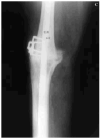

Se presentaron complicaciones postoperatorias en doce pacientes, de las cuales las más notables fueron alteraciones de la cicatrización en cinco casos, infección de la herida quirúrgica en tres y en otro hubo una parálisis del nervio ciático poplíteo externo. La consolidación se define como una fusión sólida clínicamente, con evidencia radiográfica de trabeculación ósea a través del foco de artrodesis. Se produjeron tres roturas de clavos, en uno de ellos se aplicó una ortesis y en los dos restantes se practicó un nuevo enclavado con aporte de injerto. En los tres casos se ha obtenido la consolidación a los siete meses, como promedio (Fig. 4).

Figura 4. Aflojamiento protésico. A: Radiografía preoperatoria. B: Rotura de clavo 18 meses después de la cirugía. C: Nuevo enclavado.